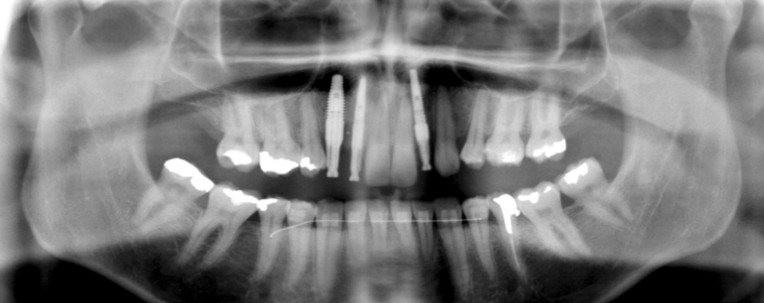

X-ray showing position of implants